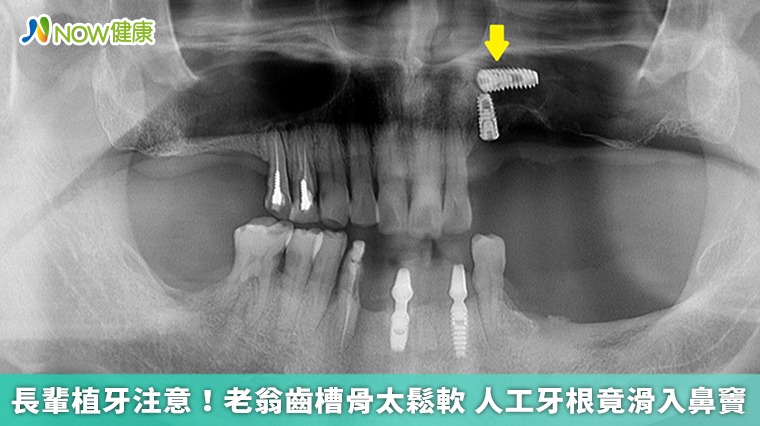

▲凌先生在人工植牙時,牙根不幸滑進鼻竇,後續到大醫院接受內視鏡微創手術處理。(圖/台北慈濟醫院提供)

【NOW健康 陳曉彤/新北報導】63歲的凌先生本身有糖尿病加上長期以來缺牙,日前在牙科診所接受左側上顎多顆人工植牙手術,由於他的上顎骨較薄,需要同時進行鼻竇增高手術,未料術中竟因齒槽骨過於鬆軟,人工牙根意外滑入左側鼻竇內。凌先生5天後被轉介到台北慈濟醫院,就醫時不僅發高燒,左側臉頰還嚴重腫脹,醫師後續採取內視鏡微創手術,終於將人工牙根從鼻竇內取出。